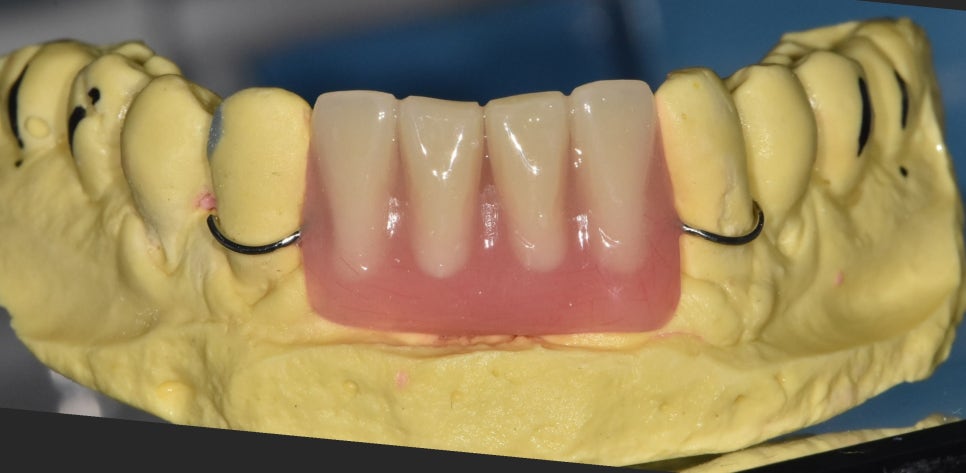

수술 당일, 일상생활에 문제가 없도록

앞니 전용 임시 틀니를 미리 제작해 드렸는데요~

이 장치는 사회생활을 위한

심미적인 용도이므로,

식사하실 때는 꼭 빼고 드셔야 합니다.

임시틀니를 끼고 식사를 하시게 되면

애써 심어놓은 임플란트 뿌리가

제대로 굳지 못하고 흔들릴 수 있기 때문에

조심하셔야 해요~

240319

꼼꼼하고 정교한 디지털 과정을 거친 덕분에

만족스러운 보철물이 완성되었네요.^^